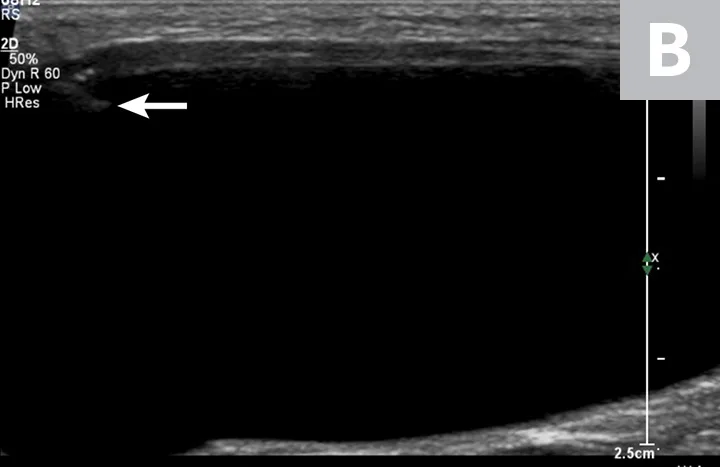

Ultrasonographic image showing the cranial aspect of the urinary bladder (A), identified just before ultrasound-guided cystocentesis. It is important to adjust the depth of the image so that the urinary bladder is focused and to consider the depth of the urinary bladder using a machine scale that should be present on the ultrasound screen; in smaller patients the needle may only be partially inserted and not reach the hub (B; arrow).